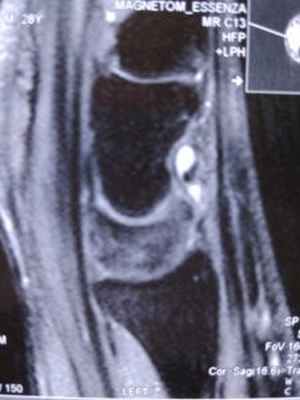

Для диагностики заболевания часто достаточно осмотра врача, однако для уточнения иногда используют УЗИ или МРТ (рентгенография в данном случае не информативна).

В редких случаях может быть использована МРТ, особенно для поиска очень маленьких гигром на тыле запястья и дифференциальной диагностики с болезнью Кинбека.